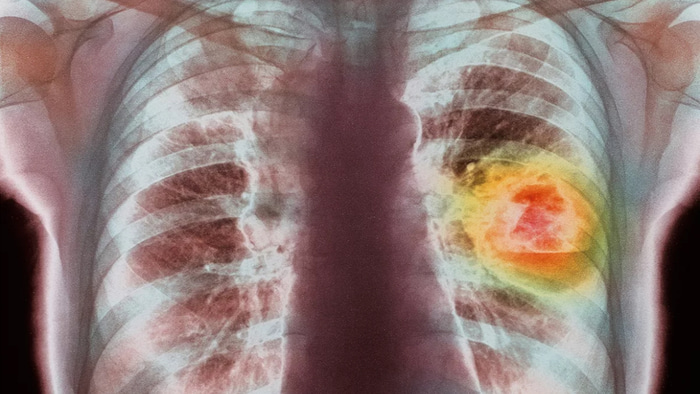

Рак легкого – разновидность рака, вызванная неконтролируемым ростом патологических клеток в тканях легких. Это серьезное заболевание, которое может нанести тяжелый урон здоровью и привести к смерти. Рак лёгкого стабильно занимает первое место в структуре онкологических заболеваний и смертности мужского населения в России. Среди мужчин он встречается чаще, чем среди женщин – 16,3 % и 3,8 % соответственно.